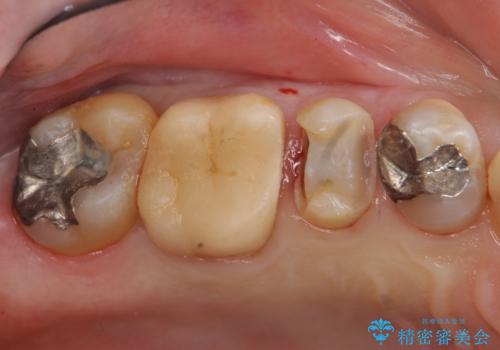

銀歯の下が虫歯 セラミックインレーに

- 銀歯の下が虫歯になっていたため、虫歯を取り、セラミックインレーで修復しました。

見るだけでは、わかりにくいのでしっかりレントゲンを診てもらえるような定期検診が大事です。

銀歯が合っていないなどは、見た目だけではわかりにくいことがあります。

早めに見つけて、症状が出る前に治すことが大事です。

歯科医師にレントゲンをしっかり診てもらうことが重要です。